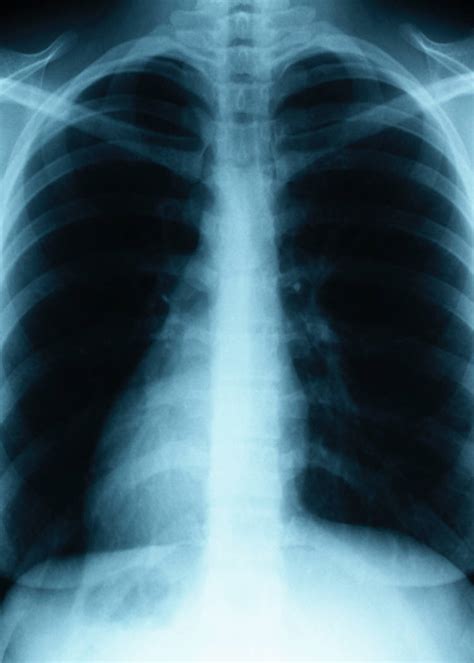

This is a common occurrence with cancers of the nasal sinus, bladder, skin, and airways in the lungs. It is also possible that a cancer diagnosis can be delayed if the cancer is mistaken for pneumonia. For this reason, lung cancer may be misdiagnosed as conditions such as pneumonia, asthma. Pneumonia can be mild and only require a week of treatment before you can. In this article they describe a variety of pulmonary conditions that can present with imaging features mimicking those of primary lung cancers.

Signs and Symptoms associated with Lung Cancer - Cancer Pro from www.cancer-pro.com Repeated respiratory infections, such as bronchitis or pneumonia, can be a sign of lung cancer. The serious medical literature contains a couple. The cancer can happen in any part of the lung tissue. These symptoms may also be present in patients who experience several types of respiratory infections and other conditions. The nhs explains that this condition is an infection of the lungs or large airways. Lung cancer most often spreads to the liver, the adrenal glands, the bones, and the brain. Pneumonia and lung cancer both occur in the lungs and share several overlapping symptoms. This is a common occurrence with cancers of the nasal sinus, bladder, skin, and airways in the lungs.

Lung cancer most often spreads to the liver, the adrenal glands, the bones, and the brain. For this reason, lung cancer may be misdiagnosed as conditions such as pneumonia, asthma. Moreover, a lung infection further compromises the ability of the lungs to function properly. Or by inserting a tube through the chest wall to drain infection (thoracostomy). One symptom of lung cancer, pointed out by the charity, is a recurring chest infection. 1) infections with tb and other bacteria, 2) exposure to toxic and/or allergenic substances such as asbestos, 3) pulmonary fibrosis, and 4) autoimmune diseases like sarcoidosis. According to roy castle lung cancer foundation (rclcf), a telltale sign your chest infection is cancerous is whether it persists. In these cases, there is, in actuality, an infection in the body, but a cancer is the real, deeper culprit. Lung cancer can also increase the risk of pneumonia by weakening the immune system. Or, you might have a chest infection that doesn't get better with treatment. Aspergillosis, cryptococcosis, and mucormycosis are the most common opportunistic fungal infections that can mimic lung cancer. However, it can occur in other heart and lung diseases. In addition, it isn't unusual for an infection to develop around a lung tumor, and the resulting pneumonia may obscure an underlying tumor.

Moreover, a lung infection further compromises the ability of the lungs to function properly. Repeated respiratory infections, such as bronchitis or pneumonia, can be a sign of lung cancer. Lung cancer is attributed to various external factors including exposure to asbestos, radon gas, and cigarette smoking. Lung cancer is the last thing a doctor thinks to look for in young, nonsmoking women, says gerold bepler, m.d., director of the comprehensive lung cancer research center at the moffitt cancer. 4, 5, 16, 17 of the patients with a history of nsclc, patients with a history of these 3 fungal infections from january 1, 2007, to may 1, 2020, were identified in starr using the addition of the following criterion. However, the symptoms of lung cancer differ vastly from bronchitis which is one of the commonest affections of chronic smokers. The cause can be bacteria, a virus, or fungi. Thank you for all your posts. Furthermore, lung cancer symptoms, such as a persistent cough, back pain or weight loss, can resemble a cold or bronchitis and may not raise suspicions of lung cancer. A chest infection is a. Or, you might have a chest infection that doesn't get better with treatment. In this article they describe a variety of pulmonary conditions that can present with imaging features mimicking those of primary lung cancers. The cancerous tumor (s) cause a decrease in normal lung cell functioning, which can block the airways of the lungs leading conditions susceptible to infections.

Clinical and epidemiologic studies have suggested a strong associati … If a chest tube is inserted, drugs can be injected into the space around the lungs to break down the divisions. However, the symptoms of lung cancer differ vastly from bronchitis which is one of the commonest affections of chronic smokers. However, it can occur in other heart and lung diseases. In this article they describe a variety of pulmonary conditions that can present with imaging features mimicking those of primary lung cancers. About 30% to 40% of people with lung cancer have some symptoms or signs of metastatic disease. The cancerous tumor (s) cause a decrease in normal lung cell functioning, which can block the airways of the lungs leading conditions susceptible to infections. Pneumonia and lung cancer both occur in the lungs and share several overlapping symptoms. Lung cancer is attributed to various external factors including exposure to asbestos, radon gas, and cigarette smoking. Lung cancer is the last thing a doctor thinks to look for in young, nonsmoking women, says gerold bepler, m.d., director of the comprehensive lung cancer research center at the moffitt cancer. Symptoms of metastatic lung tumors depend on the location and size. When tested, infection could be found when there is an underlying cancer. This is a common occurrence with cancers of the nasal sinus, bladder, skin, and airways in the lungs.